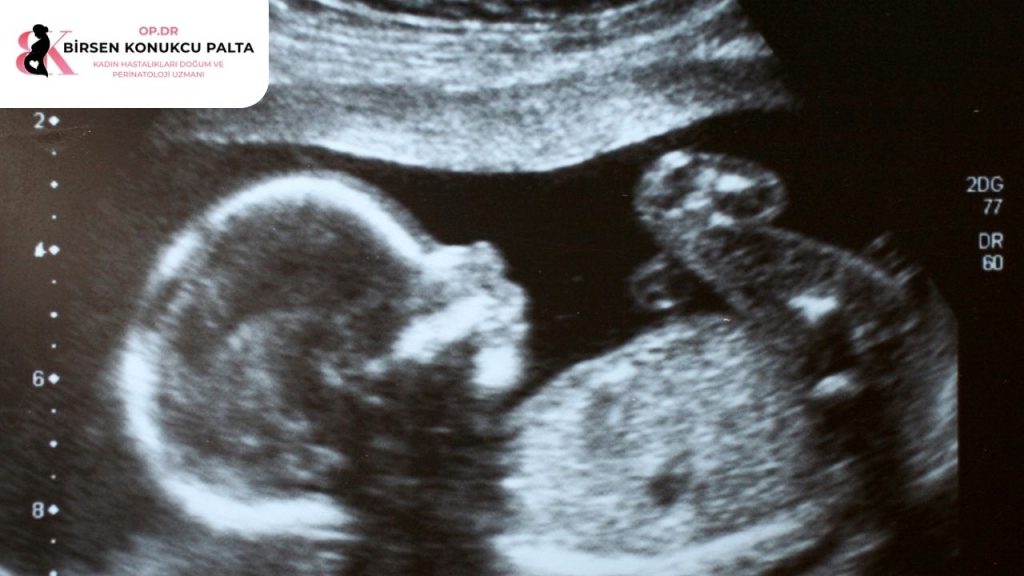

- 2D (İki Boyutlu) Ultrason: Tıbbi tanı için en temel ve kritik yöntemdir. Bebeğin iç organlarının, kemik yapısının ve anatomik gelişiminin siyah-beyaz kesitler halinde incelenmesini sağlar. Organ anomalilerinin tespiti büyük oranda bu yöntemle yapılır.

Detaylı ultrason (ayrıntılı ultrason); genellikle gebeliğin 18 ile 23. haftaları arasında yapılan, bebeğin tüm iç organlarının, beyin gelişiminin ve uzuvlarının perinatoloji uzmanı tarafından milimetrik olarak incelendiği kapsamlı bir görüntüleme yöntemidir. Amacı, bebekteki olası yapısal anomalileri tespit etmek ve gelişim takibini yapmaktır.

İşlem, standart ultrason muayenelerine benzer şekilde gerçekleştirilir. Anne adayı muayene masasına sırtüstü yatar ve karın bölgesine jel sürülür. Yüksek görüntü kalitesine sahip ultrason cihazı probu karın üzerinde gezdirilerek bebeğin anatomisi incelenir. İşlem ağrısızdır, radyasyon içermez ve ortalama 20-40 dakika sürer.